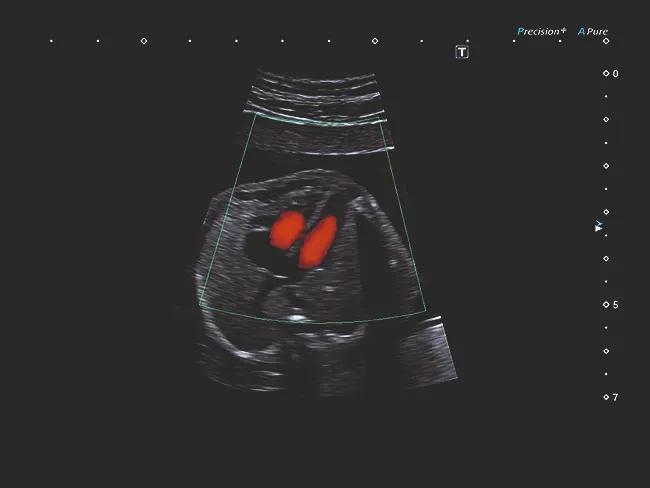

Luminance обеспечивает естественную 3D-визуализацию высокого качества и четкости, обеспечивая четкую визуальную обратную связь по глубине и детализации начиная с первого триместра беременности.